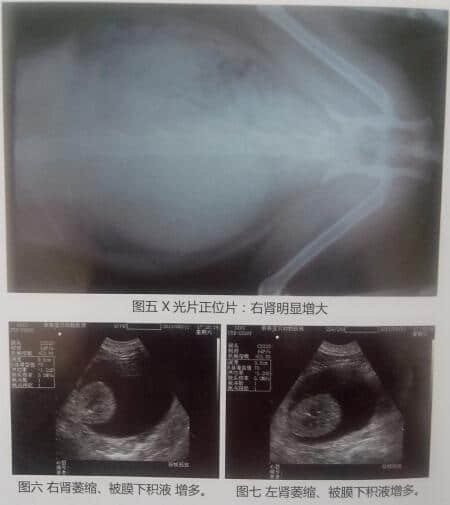

(1)放射性检查:右肾明显增大(详见图五)

(2)B超检查:双肾周囊肿、被膜下积液增多、肾脏形态变小。(详见图六、图七)

5、诊断:双肾周囊肿被膜下积液引起慢性肾衰